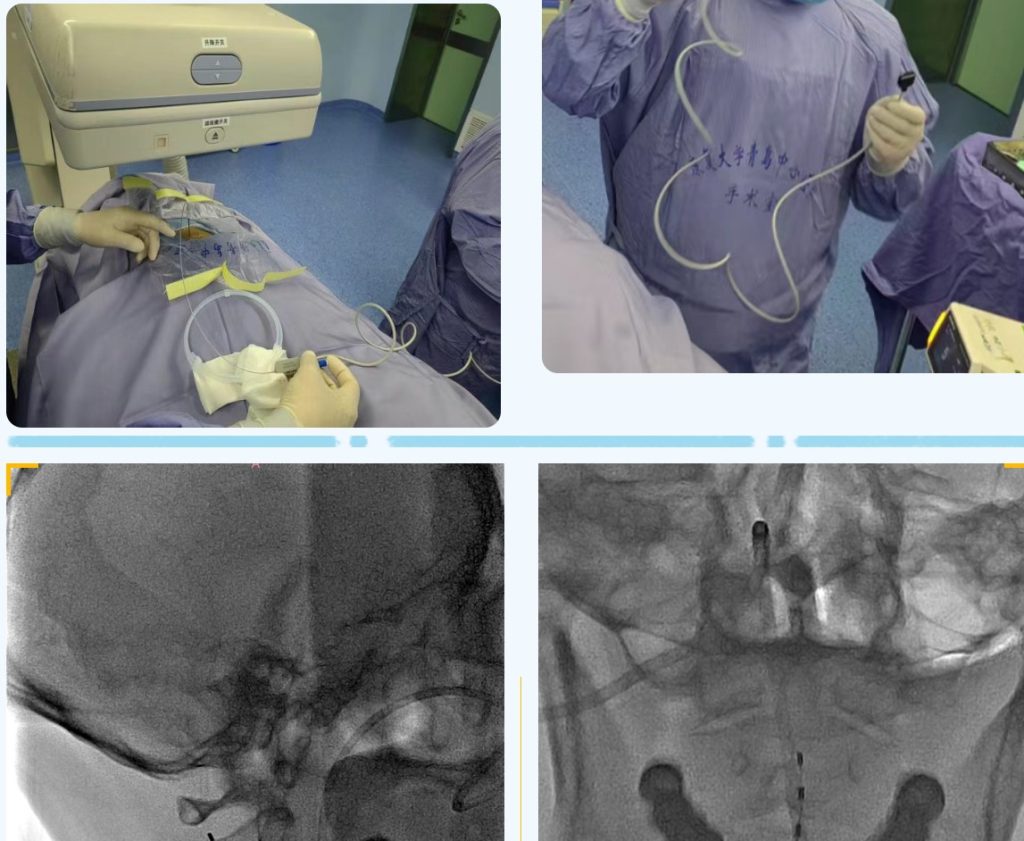

近日,康复大学青岛中心医院神经外一科赵明媚主任团队为杨先生和李先生实施了短程高颈段脊髓电刺激术,术后两周,杨先生已经能呼叫睁眼,李先生已经有双侧肢体的活动。

意识障碍主要包括植物状态(vegetative state,VS)和微意识状态(minimally consciousness state,MCS)。传统治疗方法包括药物、高压氧、康复理疗、感官及环境刺激等,但疗效均欠佳,给家庭和社会带来了长期的负担。近年来,诸多研究发现神经调控治疗可能成为治疗意识障碍的有效手段。而高颈段脊髓电刺激术就是将电极置入椎管内,以脉冲电流刺激高位颈髓从而改善意识障碍患者意识状态的一种治疗手段。脊髓电刺激术可分为短时程、长时程两种。短程脊髓电刺激术治疗具有创伤小、手术时间短、经济等优点,是除高压氧及常规康复锻炼手段后的最新促醒的外科技术之一。

短程高颈段脊髓电刺激术可以增加脑血流灌注、减轻脑内氧化应激反应,激活脑干网状结构上行激动系统及增加大脑皮层活动。通过2-4周的作用时间,从而改善病人的意识状态。如果短时程治疗效果好,可以进一步做长时程治疗。巩固治疗效果,持续改善病人的昏迷症状。